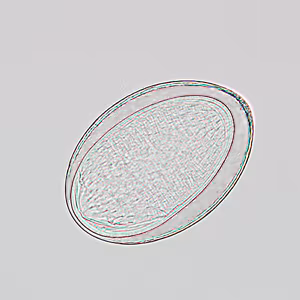

Eggs of Moniliformis moniliformis.

Moniliformis moniliformis eggs are 90–125 µm long by 65 µm wide. They are elongate-oval and have a thick, clear shell. Eggs are shed in feces and contain a larva (acanthor) that possesses rostellar hooks. The normal definitive hosts for M. moniliformis are rodents, including rats. Adults seldom mature in the human host. When adults do reach maturity in the human host, they rarely produce eggs, so eggs are not usually found in the feces of infected humans.